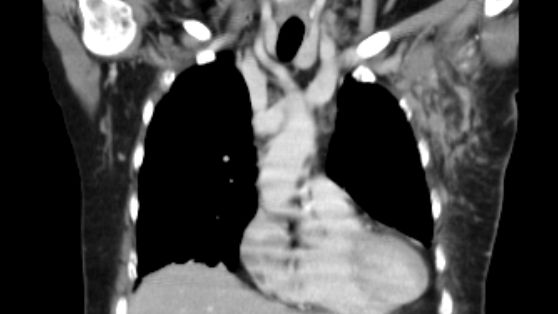

Koronares CT mit Darstellung zahlreicher Lymphknotenmetastasen links axillär

52-jährige Frau mit exulzeriertem, blutendem Mammakarzinom T4b N3a M1. 14 extrirpierte LK tumorhaltig. R2-Resektion wegen Ummauerung der Axillagefäße.